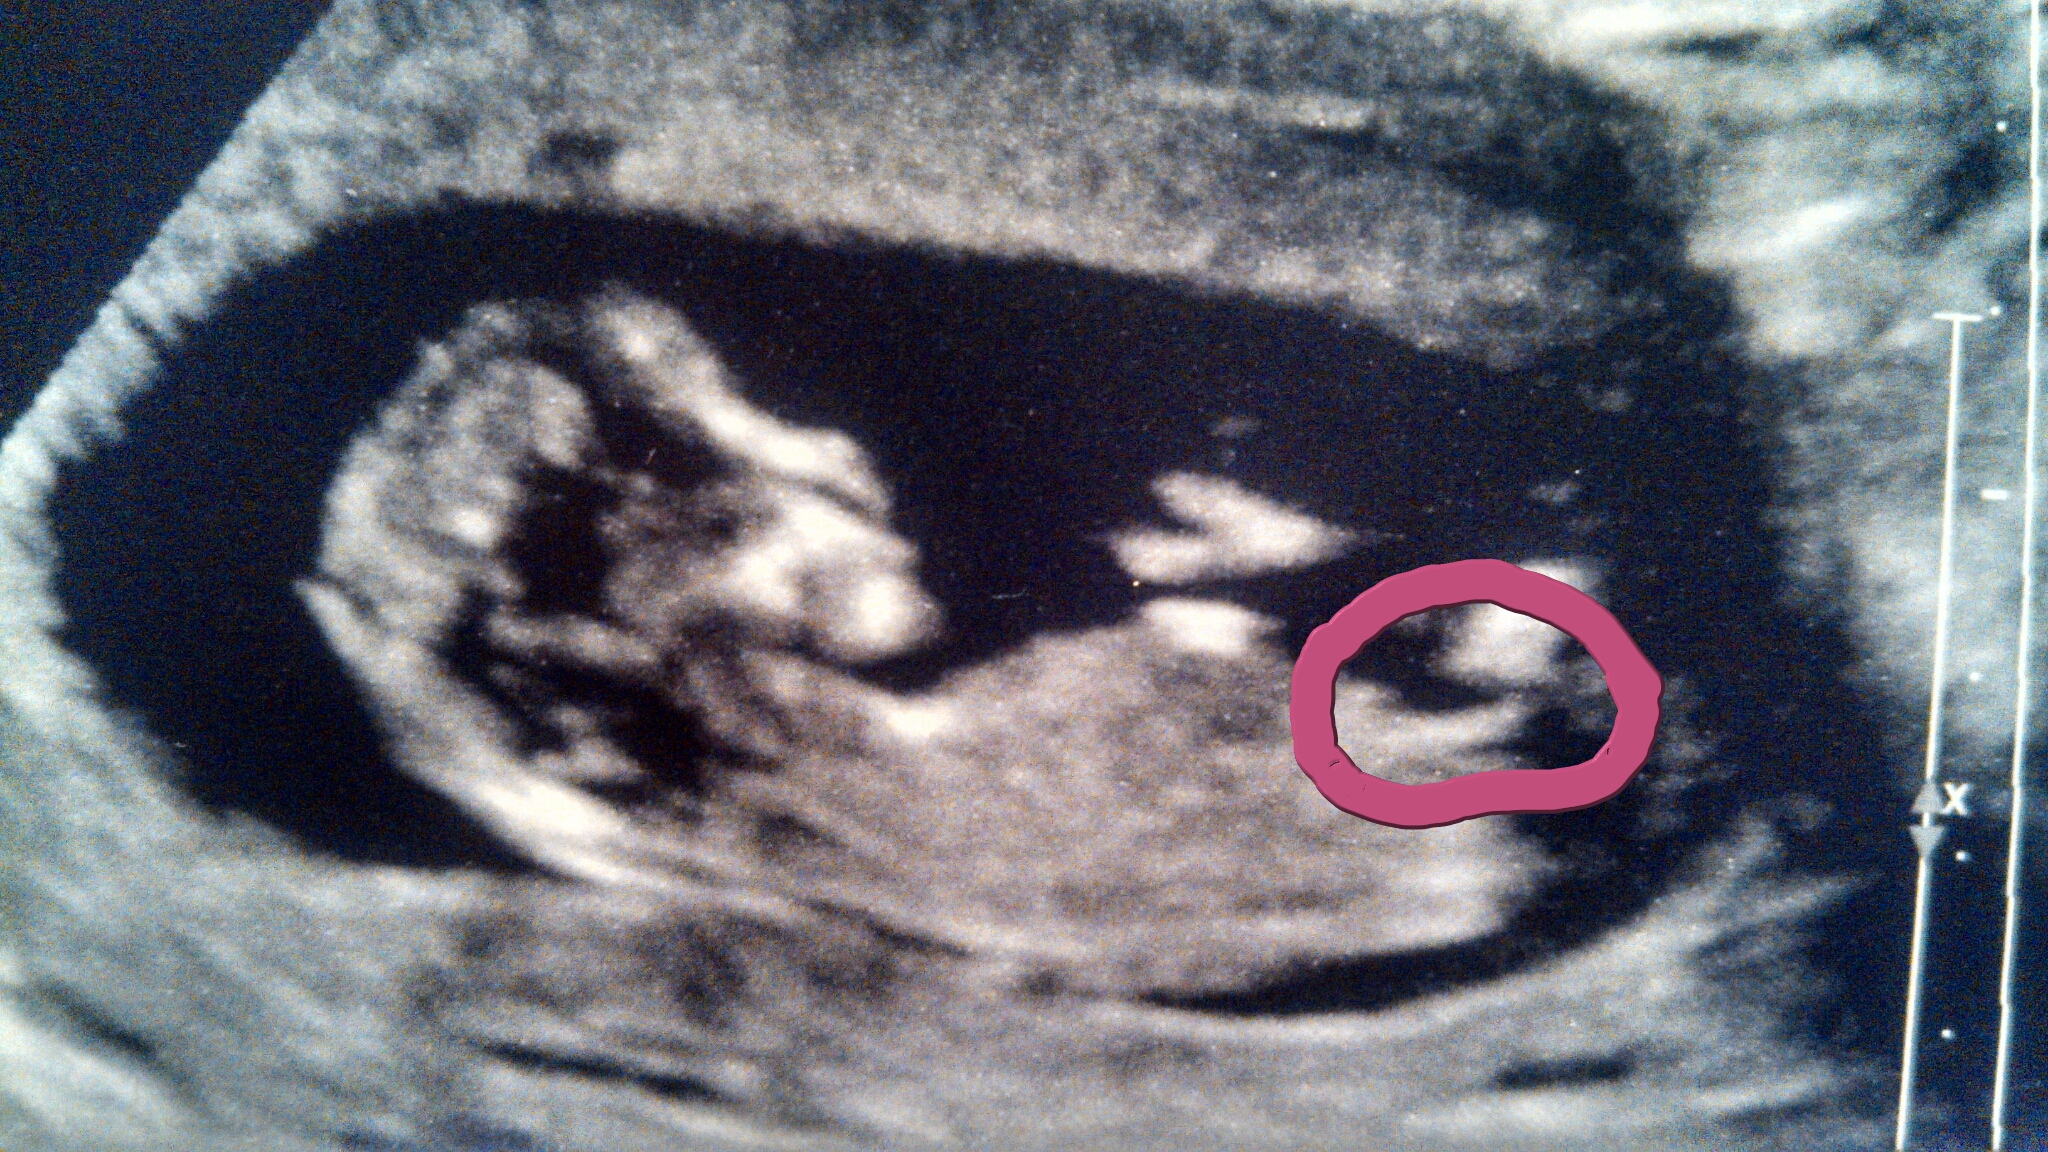

I really think the 3rd time's the charm and our GIRL gender sway worked after 2 beautiful boys. Nub/skull pics are from 13 weeks. Please make my day with some input, thanks :)

I'm not 100% sure that's the nub....sorry I can't make a good guess....fingers crossed it's your pink bundle x

I'm sorry if thats the nub I would Actualy lean to boy. But I find it hard to see.

I agree with Sweetdream it's pretty angled I would say boy I hope we are wrong

I hate to say it but I agree that I'd lean boy. There is an angle to the nub looking at the spine and the shadow on top that could be a stacked nub is esp what makes me think boy. Either way you have a very cute baby!

I hate to say this but it could go either way, but I would have to lean boy if I must guess.

The truth is though, you don't have a good image of the nub itself (the end). Its very blurry. I think I could more accurately guess if the nub was clear.

The only reason I slightly lean boy is because the shaft part is slightly angled because it has risen slightly from the body. Usually girl nubs (even if they looked slightly angled) have not risen from the body -- there is no black space under the shaft part.

I agree I don't think that's the nub circled but hope you hear pink xx